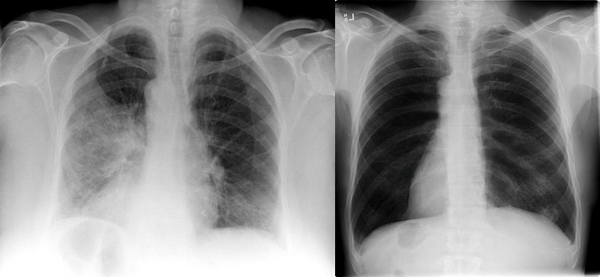

“l’ve spent most of my career on construction sites, constantly exposed to dust and airborne pollutants. Over time, it caught up with me-l developed COPD. At first, it was just mild shortness of breath, but the symptoms slowly worsened.l found myself coughing regularly, wheezing, and relying on an inhaler just to get through the day. Even climbing stairs became a challenge. My doctor warned me that if l didn’t take action, my condition could severely impact my quality of life.”

“By the fourth week, the tightness in my chest had lessened dramatically.l had more energy, and my doctor was surprised to see such a reduction in lung inflammation. Even my family noticedl wasn’t using my inhaler as much and seemed more active and upbeat.”

Now, seven weeks in, l can say with confidence that Mullein Aroma Diffuser has changed my life. My lungs feel stronger. The coughing,wheezing, and constant fatigue are gone.l can walk. play with my kids, and enjoy the outdoors again-without struggling to catch my breath. This product gave me back the ability to live fully.l recommend it to anyone battling COPD or breathing difficulties.lt brought me not just relief_but real hope.“